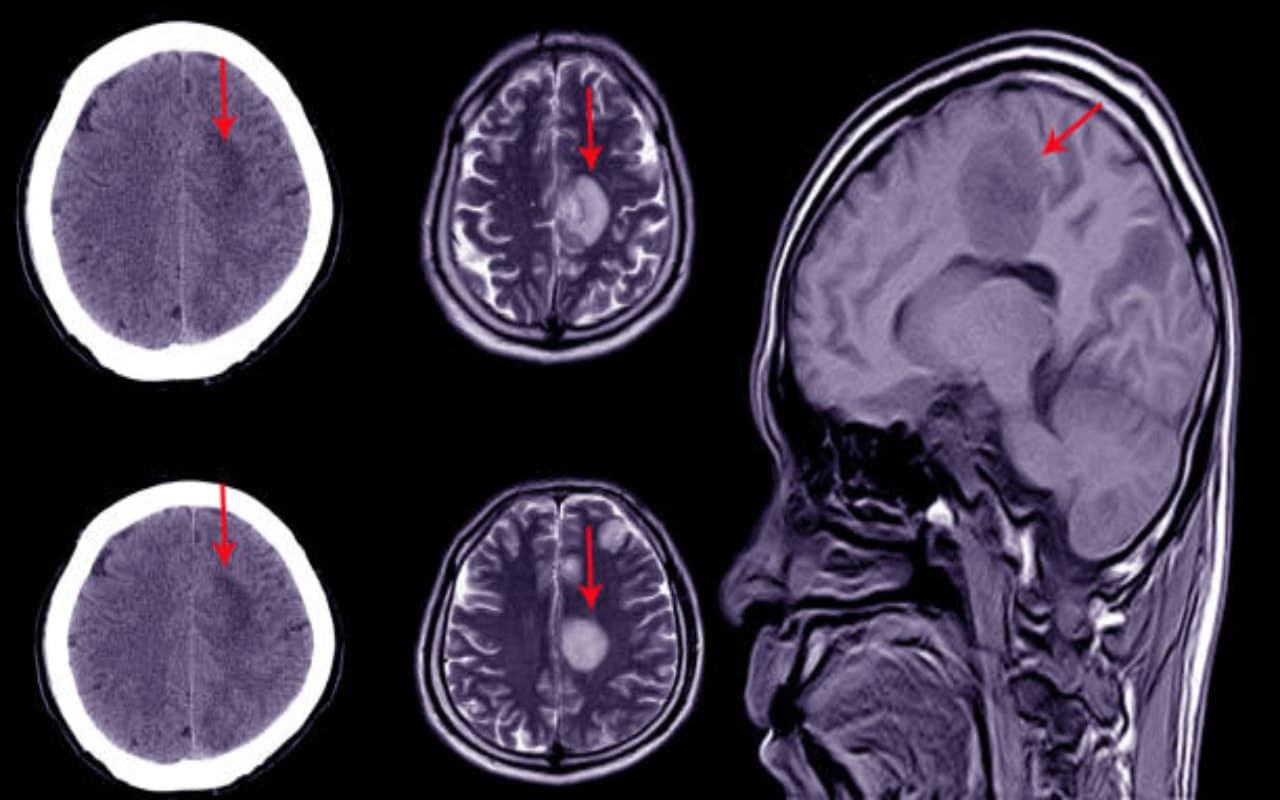

भारतीय स्वास्थ्य मंत्रालय के आंकड़ों के अनुसार भारत में विकलांगता और मृत्यु दर का एक प्रमुख कारण ट्रॉमैटिक ब्रेन इंज्यूरी है. आंकड़ें इसलिए डराने वाले हैं क्योंकि ये बताते हैं कि भारत में हर साल 10 लाख से अधिक लोग कारण ट्रॉमैटिक ब्रेन इंज्यूरी से पीड़ित होते हैं, जिसकी वजह से हर साल लगभग एक लाख मौतें होती हैं. ब्रेन एंड स्पाइन पीपीएल, नई दिल्ली के वरिष्ठ सलाहकार डॉ यशपाल सिंह बुंदेला ने ट्रॉमैटिक ब्रेन इंज्यूरी के बारे में बात करते हुए कहा कि निश्चित तौर पर यह समस्या भारत में बहुत बड़ी हो गई है. लेकिन यहां ध्यान देने वाली बात यह भी है कि मस्तिष्क के गंभीर चोट के मामलों में चिकित्सा सुविधा उपलब्ध हो सकती है. अगर मरीज को समय पर न्यूरोसर्जरी की सुविधा मिल जाए तो रोगी को बचाया जा सकता है और कई मामलों में परिणाम काफी हद तक सकारात्मक हो सकते हैं. न्यूरीसर्जरी के जरिए मस्तिष्क के भीतर रक्तस्राव या चोट का इलाज संभव है और यह उस परिस्थिति की आवश्यकता भी है. ऐसे मामलों के लिए भारत में उपयोग की जाने वाली स्थापित सर्जिकल प्रक्रियाओं में से एक – डीकंप्रेसिव क्रैनिएक्टोमी (डीसी) है. इस प्रक्रिया में इंट्राक्रैनील दबाव को कम करने और गंभीर चोट की स्थिति में खोपड़ी के क्षतिग्रस्त हिस्से को सावधानीपूर्वक निकालना है ताकि चोट को और गंभीर होने से रोका जा सके.

डॉ वैश्य ने मस्तिष्क के गंभीर चोट के इलाज में डिकंप्रेसिव क्रैनिएक्टोमी को सबसे बेहतरीन तरीका बताया है. उन्होंने कहा कि ट्रॉमैटिक ब्रेन इंज्यूरी के इलाज में यह न्यूरोसर्जरी के शस्त्रागार का सबसे शक्तिशाली उपकरण है. इंट्राक्रैनियल दबाव को कम करके हम चोट को अन्य गंभीर चोट में बदलने से रोक सकते हैं.इसका सकारात्मक परिणाम यह होता है कि हम रोगी को जीवित रख सकते हैं और उसके स्वस्थ होने की संभावना भी बढ़ जाती है.हालांकि, इस प्रक्रिया की सफलता काफी हद तक है सही समय पर इलाज मुहैया कराने पर निर्भर है.